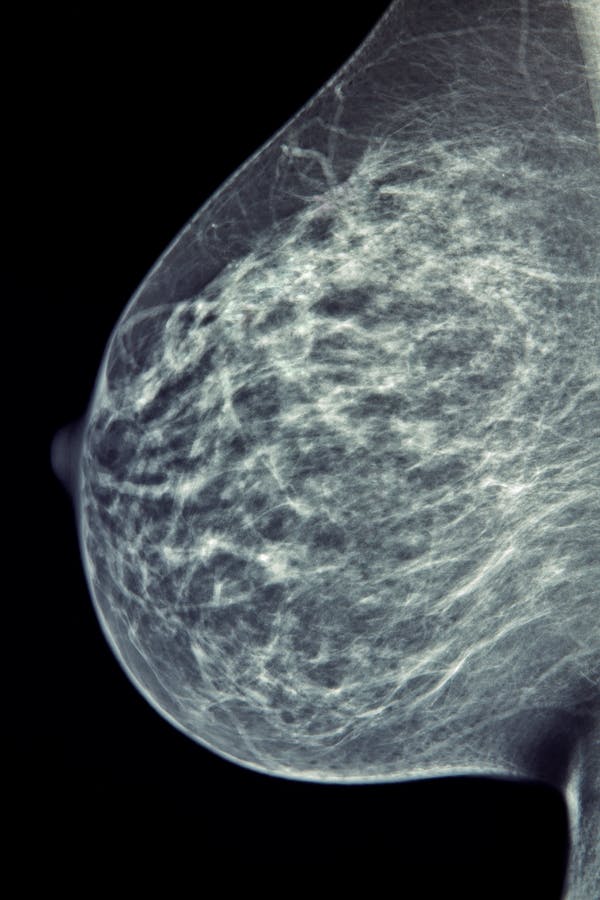

Bust cancer cells is one of the most typical cancer cells in the UK. It represent 15% of all brand-new situations in the nation, and regarding one in 8 ladies will be identified with it throughout their life time. In the NHS, bust cancer cells testing regularly consists of a mammogram, which is basically an X-ray of the bust.

Interpreting a mammogram is a complicated procedure typically carried out by specifically qualified radiologists and radiographers. Their abilities are important to the very early discovery and medical diagnosis of this cancer cells. They aesthetically scrutinise batches of mammograms in a session for indications of bust cancer cells.

However these indications are frequently ambiguous or difficult to see. Incorrect unfavorable prices – where cancers cells are improperly identified or missed out on – are in between 20 and 30% for mammography. These are either mistakes in understanding or mistakes in analysis, and could be associated to the level of sensitivity or specificity of the visitor.

For bust cancer cells, the concentrate up until now has gotten on exactly just how AI could assistance identify the illness from mammograms. Every mammogram is check out by 2 experts, which could result in prospective hold-ups in medical diagnosis if there's a shortfall in proficiency. However scientists have been taking a look at presenting AI systems at the moment of the testing. The concept is that it would certainly assistance a specialist's searchings for without waiting on the 2nd viewpoint of one more expert. This would certainly decrease the waiting time and connected stress and anxiousness for the ladies that have been evaluated.

AI has currently made considerable strides in cancer cells picture acknowledgment. In late 2018, scientists reported that a person industrial system matched the precision of over 28,000 interpretations of testing mammograms by 101 radiologists. This implies it accomplished a cancer cells discovery precision similar to a professional radiologist.